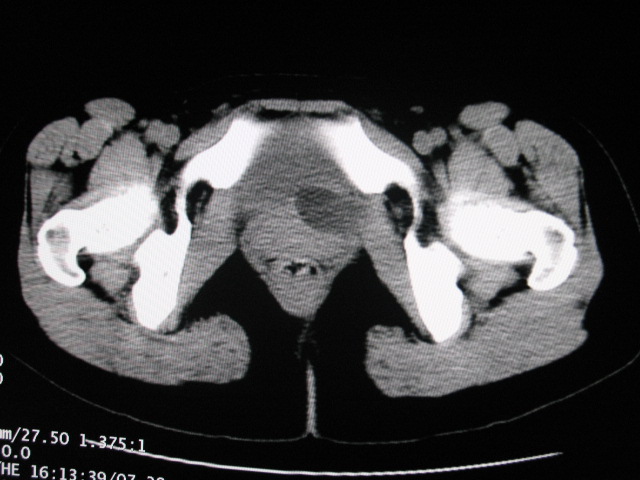

女,28岁,自觉腹部包块一年余

左侧为扩张的输尿管,一直延续到膀胱,那么它的上端应该是扩张的肾盂,但是在他的下方我们看到一个比较正常的肾,所以考虑左侧重复肾盂输尿管畸形。

考虑左侧双肾盂双输尿管畸形,其中一输尿管末端梗阻(不排除异位开口可能)并相应之肾盂及输尿管明显扩张积水。

考虑左侧双肾盂双输尿管畸形,其中一输尿管末端梗阻并输尿管肠管样扩张盂曲、肾盂囊状扩张积水。

左侧重复肾、双输尿管畸形。重复肾一般上位肾发育不良,易合并积水。

考虑左侧双肾盂双输尿管畸形,其中一输尿管末端梗阻(不排除异位开口可能,不知病人有无不自觉溢尿,有可能开口于阴道或宫颈,也可下端为盲端)并相应之肾盂及输尿管明显扩张积水。

术后证实是左侧双肾盂双输尿管畸形,巨输尿管巨肾盂症